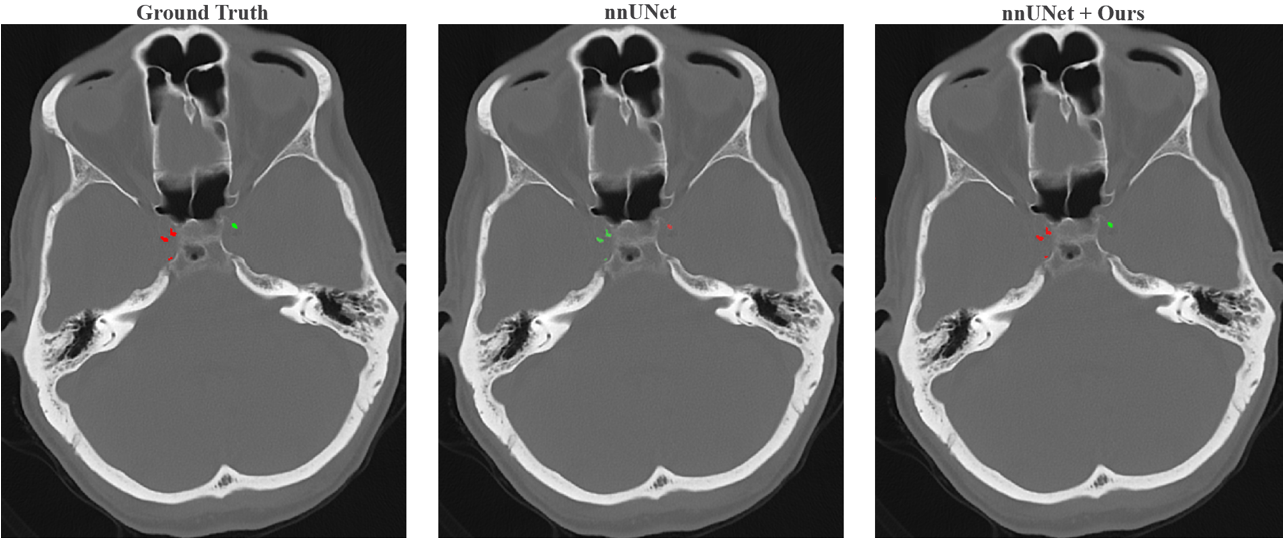

Yet, achieving this level of analysis has remained technically challenging. Manual segmentation is laborious for large-scale research. More fundamentally, a direct end-to-end approach is confounded by perceptual aliasing: the local texture and morphology of a calcified plaque are similar regardless of its anatomical segment. The identity of a plaque is therefore not defined by its appearance, but by its global anatomical context. This can lead to catastrophic localization errors; for instance, as vividly illustrated in Figure 2, a standard patch-based model lacking this context frequently mislabels entire sections of the left carotid artery as the right, and vice-versa. This failure stems directly from the fundamental dilemma of conventional 3D models: to gain the necessary global context, they must drastically downsample the volume, which erases the landmark details they need to identify. Conversely, processing high-resolution patches preserves detail but sacrifices the long-range contextual cues required to resolve the perceptual ambiguity.

Refer to caption

Figure 2: The Failure of Patch-Based Models in Tasks Requiring Global Context. (Left) Ground truth labels for left (green) and right (red) ICA segments. (Center) A standard patch-based model (nnU-Net) catastrophically mislabels the hemispheres due to a lack of global context. (Right) Our proposed method correctly utilizes global information to assign anatomically correct labels.